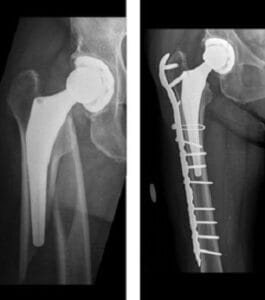

Surgical Treatment Options

- Open Reduction and Internal Fixation (ORIF):

If the implant remains firmly anchored in the femur, ORIF may be recommended. During this procedure:- Bone fragments are realigned (reduced) to their natural position.

- Special screws, cables, or metal plates are used to secure the bone externally.

- In some instances, bone grafting may be performed to support healing. Most often, allograft bone (donor bone that has been sterilized) is used to reinforce weakened areas.

- Revision Surgery:

If the implant is loose, it may be necessary to replace some or all components of the hip replacement. - Combined Approach:

In certain cases, both revision surgery and internal fixation may be required to achieve optimal outcomes.

Revision Surgery for Periprosthetic Hip Fractures

In some instances of periprosthetic hip fractures, the implant stem becomes loose. When this occurs, the existing implant must be removed and replaced with a new one in a procedure known as revision total hip replacement.

This type of surgery often requires specialized implant components. The replacement implant typically features a longer stem to provide additional stability. In certain cases, a bone graft using cadaver bone (allograft) may be utilized to strengthen or replace areas of weakened or missing bone, ensuring proper structural support for the new implant.